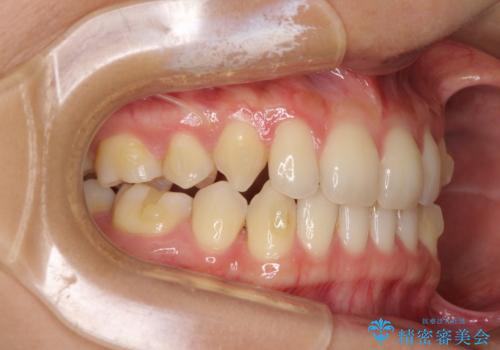

- 以前の矯正治療の後戻りにより、上の前歯にスペースができたことを気にして来院された患者様です。

インビザラインを用いて前歯のスペースを閉じつつ、上下の咬み合わせを構築していくこととしました。

隙間の空いてしまった前歯は、矯正治療で治療を行っても後戻りが起こりやすい傾向にあります。

マウスピースの保定装置をしっかりと装着しても空いてしまうため、細いワイヤーによる保定を併用することで後戻りを防止しています。